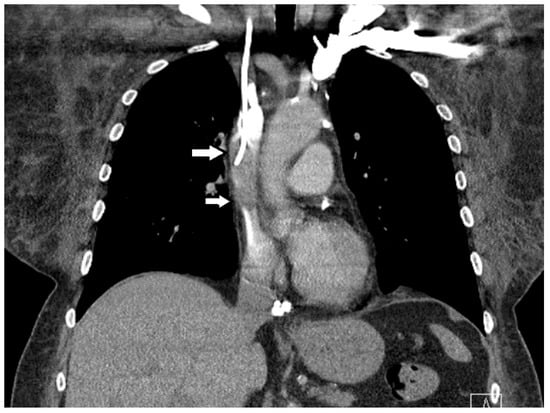

3. Case Presentation